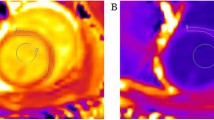

Gating the data acquisition with strong R wave on the EKG signal resulted in the LV attaining maximum volume at phase 1 of the cardiac cycle in both control and diabetic rats. Hence this maximum was taken as the LV end-diastolic volume (Fig. 1). The mean LV end-diastolic volume in the control group was 579.7 ± 8.4 μl, while the diabetic group showed a significantly (P < 0.01) decreased value of 419.4 ± 5.4 μl (Fig. 2).

Representative end-diastolic and end-systolic cine MR images of left ventricle (LV) from control and diabetic rats Typical slices of LV along the cardiac short axis obtained during end diastole and end systole from age-matched control and diabetic rats (8 weeks diabetes duration) are shown. The blood and the endocardium are clearly distinguished during both phases by the contrast provided by high resolution MRI.

The LV end-systolic volume was taken as the lowest cardiac cycle phase volume which occurred at phase 6 in both control and diabetic rats (Fig. 1). The mean LV end-systolic volume was 206.7 ± 7.0 μl in the control group and it was significantly (P < 0.01) increased in the diabetic group (226.3 ± 5.3 μl) (Fig. 2).